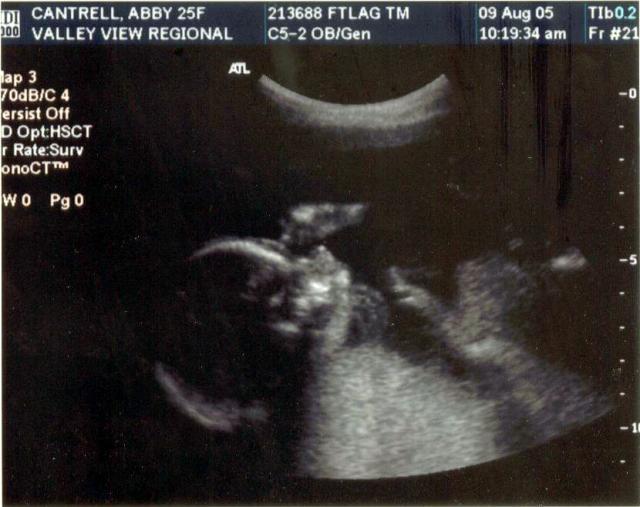

20 week ultrasound ~ Baby's profile with hand up by his or her face